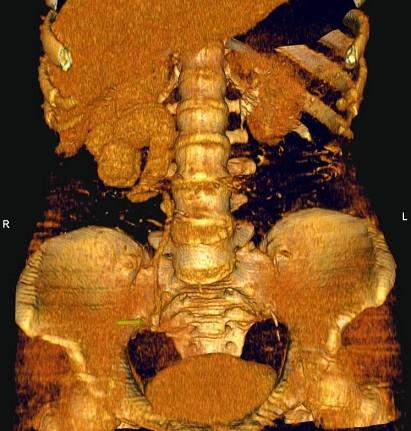

问题 女,42岁,反复右下腹部绞痛向会阴部放射1 月,CT检查如图示,下列诊断正确的是 ( )

选项 A、右侧输尿管下段结核,其上方输尿管扩张积水 B、右侧输尿管下段炎性狭窄,其上方输尿管扩张积水 C、右侧输尿管中段结石,其上方输尿管扩张积水 D、右侧输尿管下段结石,其上方输尿管扩张积水 E、右侧输尿管上段结石,其上方输尿管扩张积水

答案 C